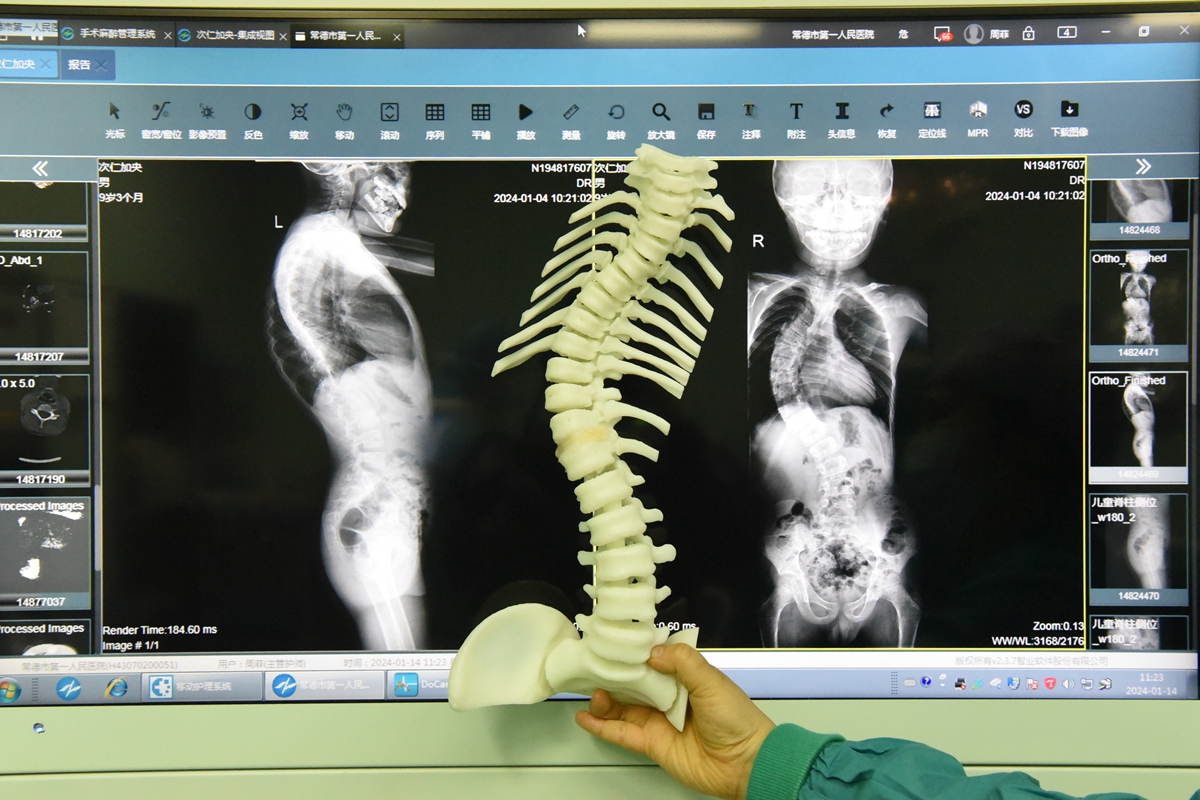

次仁加央术前影像资料及3D打印脊柱模型

术前,常德一医骨科、儿科、麻醉科等多学科专家为次仁加央进行会诊,制定周密的治疗方案,运用3D打印技术制作次仁加央的脊柱模型,直观反映脊柱病变,协助制定精确的手术计划。1月14日,在术中神经电生理监测全麻下,次仁加央顺利接受脊柱侧弯矫正手术。